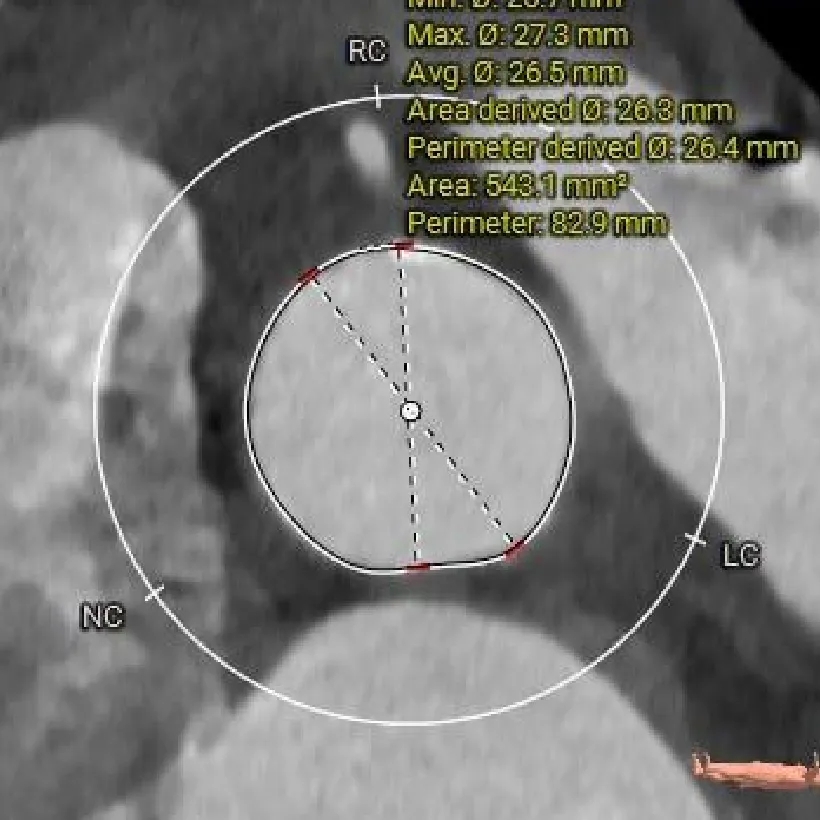

主动脉根部测量

Annulus

25mm

LVOT

钙化积分

601mm3

SOV:

28*27.8*26.8mm

STJ:

26.4mm

瓣上结构测量

瓣上2mm

瓣上4mm

25.3mm

瓣上6mm

24.2mm

瓣上8mm

24.8mm